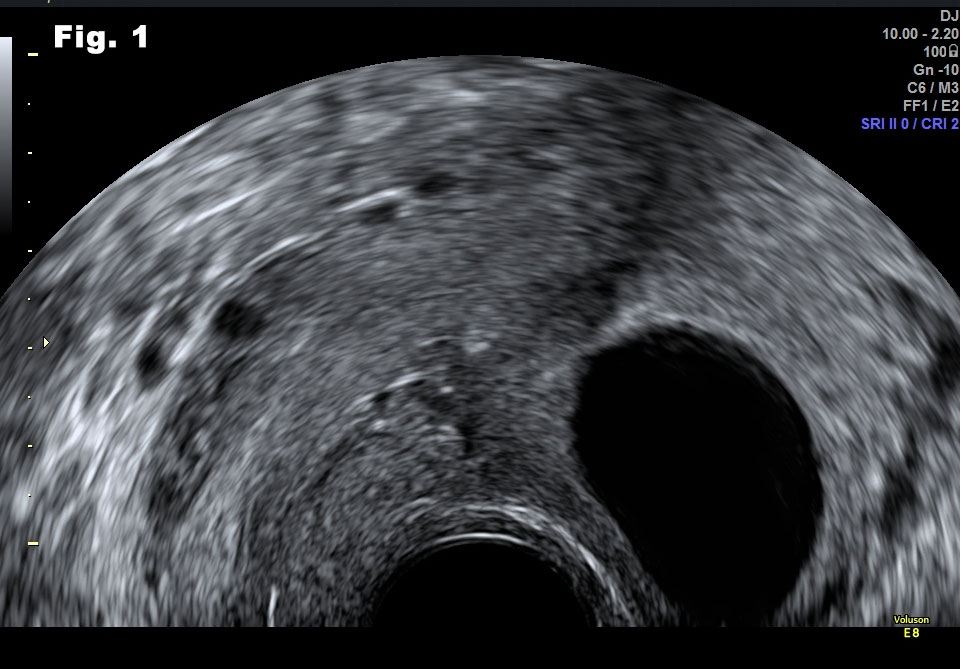

Both ovaries were morphologically normal. All pelvic organs were mobile and the patient did not complain about pain during the examination. Trans-abdominal scan confirmed the diagnosis of the transvaginal scan (fig 3, 4). All these regular, rounded and avascular masses detected on ultrasound were suggestive of benign lesions. We offered to the patient a transvaginal needle biopsy to confirm the diagnosis. Cytology of aspirated fluid was negative for malignancy and a follow up scan in six months' time was recommended.

Figure 4: Trans-abdominal scan, transverse view. Lesion and normal myometrium (white arrow) on the right.

![Cystic fibroids</br> [Feb 2017]](http://s834315022.websitehome.co.uk/wp-content/uploads/2020/11/cotm-feb2017-fig4.jpg)